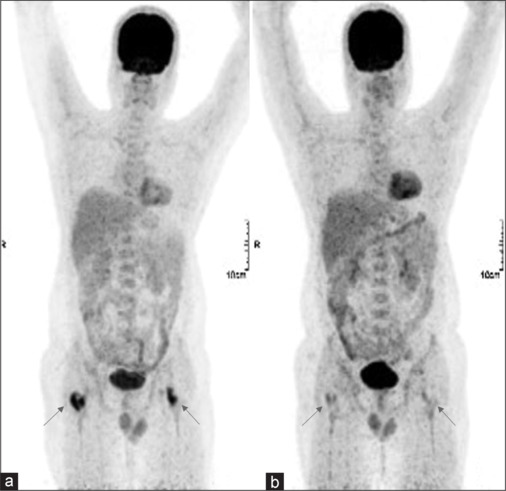

背景:朗格汉斯细胞组织细胞增多症(LCH)是一种罕见的血液系统疾病,由于其多样的临床表现,给诊断带来了重大挑战。本研究旨在分析F-18氟脱氧葡萄糖正电子发射断层扫描计算机断层扫描(F-18 FDG PET/CT)在LCH的诊断、分期和治疗中的应用。材料与方法:纳入59例LCH患者,共进行了93次F-18 FDG PET/CT扫描(包括19例随访扫描)。评估FDG摄取异常部位,并测量所有扫描的最大标准化摄取值。结果:单系统LCH 25例(42.4%),多系统累及LCH 34例(57.6%),49/59。LCH最常见的受累部位为骨骼(49/59,83.1%)和淋巴结(39/59,44.9%)。单发SS-LCH骨病变12/59(20.3%),以颅骨为主。其他常见受累部位包括肺、肝、脾、骨髓、皮肤和软组织。较不常见的受累部位包括胰腺(2例)、枕叶(1例)和肠(1例)。PET/CT用于19例患者的疗效评估,并帮助疾病进展(2例)和复发(2例)的患者启动二线化疗。7例临床怀疑为LCH,根据病变特征和FDG摄取情况诊断为LCH,并经活检证实。结论:F-18 FDG PET/CT显示了LCH病变的形态学和代谢特征,有助于准确诊断、评估疾病负担和预测预后,可作为LCH治疗的综合影像学工具。

Results: Twenty-five patients (42.4%) had single system LCH (SS-LCH) and 34 patients (57.6%) had multisystem involvement LCH, 49/59. The most common sites of LCH involvement were bones (49/59, 83.1%) and lymph nodes (39/59, 44.9%). 12/59 patients (20.3%) had unifocal SS-LCH bone lesions, mostly in skull. The other common sites involved were lungs, liver, spleen, marrow, skin, and soft tissues. Less commonly involved sites included pancreas (2 cases), occipital lobe (1 case), and bowel (1 case). PET/CT was used in response assessment in 19 patients and helped in initiation of second line chemotherapy in cases of disease progression (2 cases) and relapse (2 cases). Seven cases with clinical suspicion were diagnosed as LCH based on lesion characteristics and FDG uptake, which were later biopsy proven.